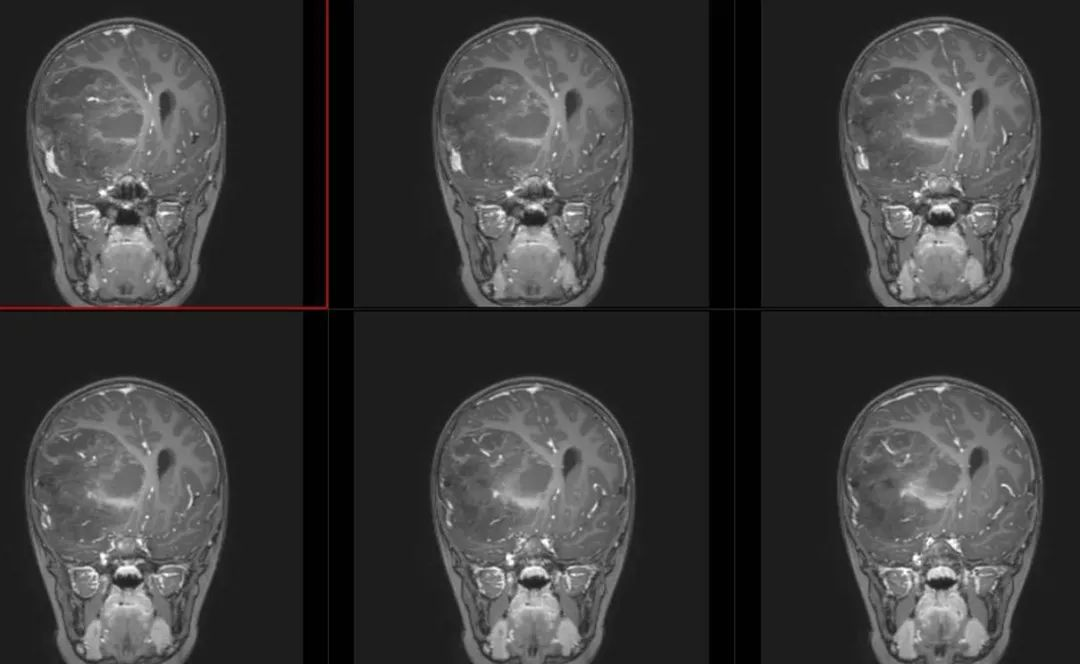

术前影像

术前T1冠状位

术前T1冠状位增强